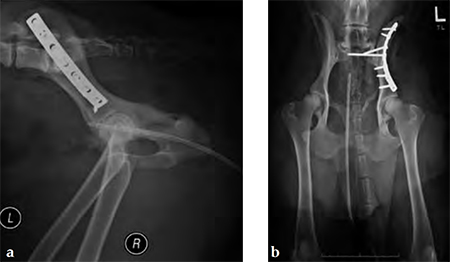

A 4-year-old Gordon setter suffered a road traffic accident and sustained multiple pelvic fractures.

(Case provided by Michael Kowaleski, North Grafton, USA)

A 7-hole 3.5 mm LC-DCP was applied and two screws were inserted into the sacral body to improve fixation strength in the cranial ilial segment. This bone is quite thin thus note that the screws #1 and #2 are quite short, screws #3 and #4 are the sacral screws and are much longer; the fracture is between screws #4 and #5 (see figure 4a-b)). The opacity on midline in the x-rays is a urinary catheter.